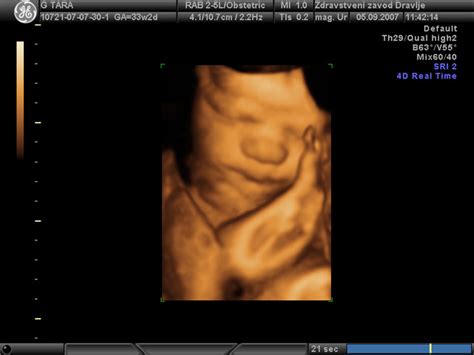

Kot možnost ob medenični vstavi se ponuja zunanji obrat ploda, pri katerem skušajo dojenčka obrniti v glavično vstavo. Ta postopek je uspešen v približno 50 % primerov. Če se dojenček kljub temu ne obrne, se z nosečnico pogovorijo o možnosti vaginalnega poroda ali načrtovanega carskega reza. Po izkušnjah nekaterih zdravnikov se večina nosečnic v takšnem primeru raje odloči za carski rez. Pogoji za vaginalni porod v medenični vstavi vključujejo primerno ultrazvočno velikost in težo dojenčka, odsotnost ovite popkovnice okoli vratu in sklonjen položaj glavice.

Ponekod v tujini opravljajo carski rez tudi na željo nosečnice, medtem ko se v Sloveniji carski rez na željo ne izvaja. V primeru nosečnosti s plodom v medenični vstavi se lahko datum elektivnega carskega reza določi teden do dva vnaprej. Nosečnica opravi pogovor s porodničarjem, UZ pregled in CTG. Pred operacijo opravijo predoperativne preiskave, vključno s krvnimi preiskavami in EKG. V kolikor se pričakuje večjo izgubo krvi, se rezervira tudi kri za morebitno transfuzijo.